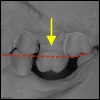

Verzahnung Die Folge von Zahnkippung und Zahnelongation is...

Gelenk Probleme Schmerzen im Gelenkbereich sind oftmals die Fol...

Knochenabbau Der Aufbau unseres gesamten Körpers ist sehr ök...